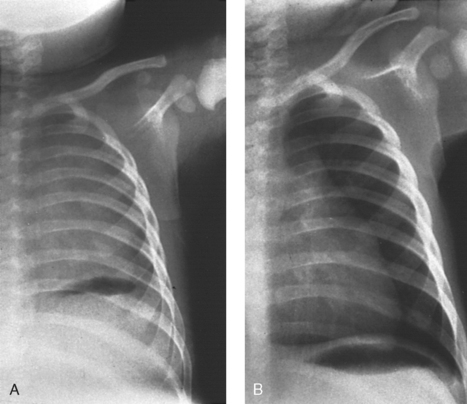

Structures shown: This projection shows the anatomy of the thorax, including the heart; trachea; diaphragmatic domes; and, most importantly, the entire lung fields, including vascular markings (Fig. 28-11).

Fig. 28-11 Mobile AP chest radiographs in critically ill patients. A, Patient with postoperative left thoracotomy and chest tube, infiltrate or atelectasis in the left base, segmental elevation of the right hemidiaphragm, and soft tissue emphysema on the left. B, Patient with small left pleural effusion and moderate right effusion, cardiomegaly, mild pulmonary vascular congestion, and calcification and torsion of the aorta.

Structures shown: This projection shows the anatomy of the thorax, including the entire lung fields and any air or fluid levels that may be present (Fig. 28-13).

Fig. 28-13 Mobile AP chest radiographs performed in lateral decubitus positions in critically ill patients. A, Left lateral decubitus position. The patient has a large right pleural effusion (arrow) and no left effusion. Complete left side of thorax is visualized because of elevation on a block. B, Right lateral decubitus position. The patient has right pleural effusion (arrows), cardiomegaly, and mild pulmonary vascular congestion. Complete right side of thorax is visualized because of elevation on a block.